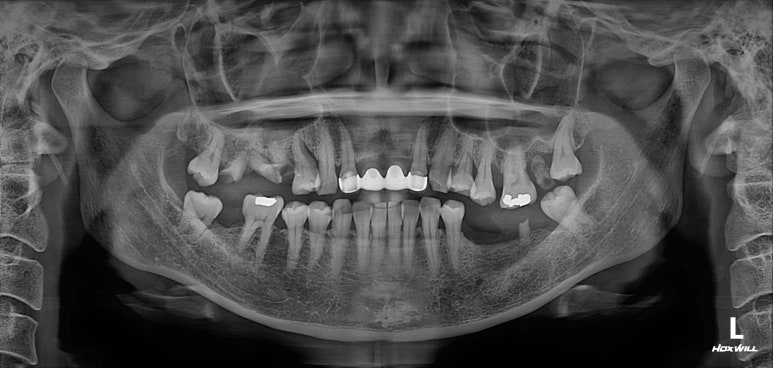

그렇게해서 최종완료 후 치과용 파노라마 사진입니다!

치과치료에 대해 잘 모르시는 분이라 할지라도 보고 있으면, 치료가 조화롭게 잘 끝났구나.. 라고 아실 수 있으리라 생각합니다.

제가 제일 좋아하는 치과용 파노라마 비교 사진입니다.

앞으로 나란히를 한 것 같이 평행한 임플란트의 완성도는 항상 카타르시스를 느끼게 합니다.

정말 어디하나 나무랄 것 없이 치료가 잘 마무리되었는데, 물론 정말 열심히 정성들여 수술하는 저도 칭찬받아야 마땅하지만 늘 묵묵히 열심히 크라운 치료를 잘 해주는 우리 보철과 전문의 원장님들께 그 공을 돌리고 싶습니다.